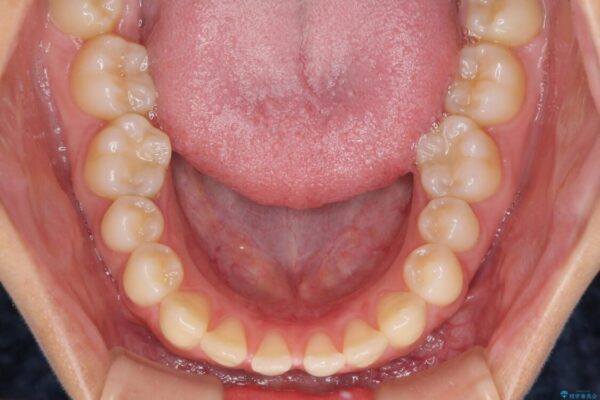

治療後

• 隙間だらけの歯列 インビザラインで改善 治療後画像